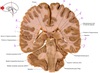

1

Q

a

body of corpus callosum

2

b

Anterior horn of lateral ventricle

3

c

Septum pellucidum

4

d

Rostrum of corpus callosum

5

e

Head of caudate nucleus

6

f

Anterior limb of internal capsule

7

g

Putamen

8

h